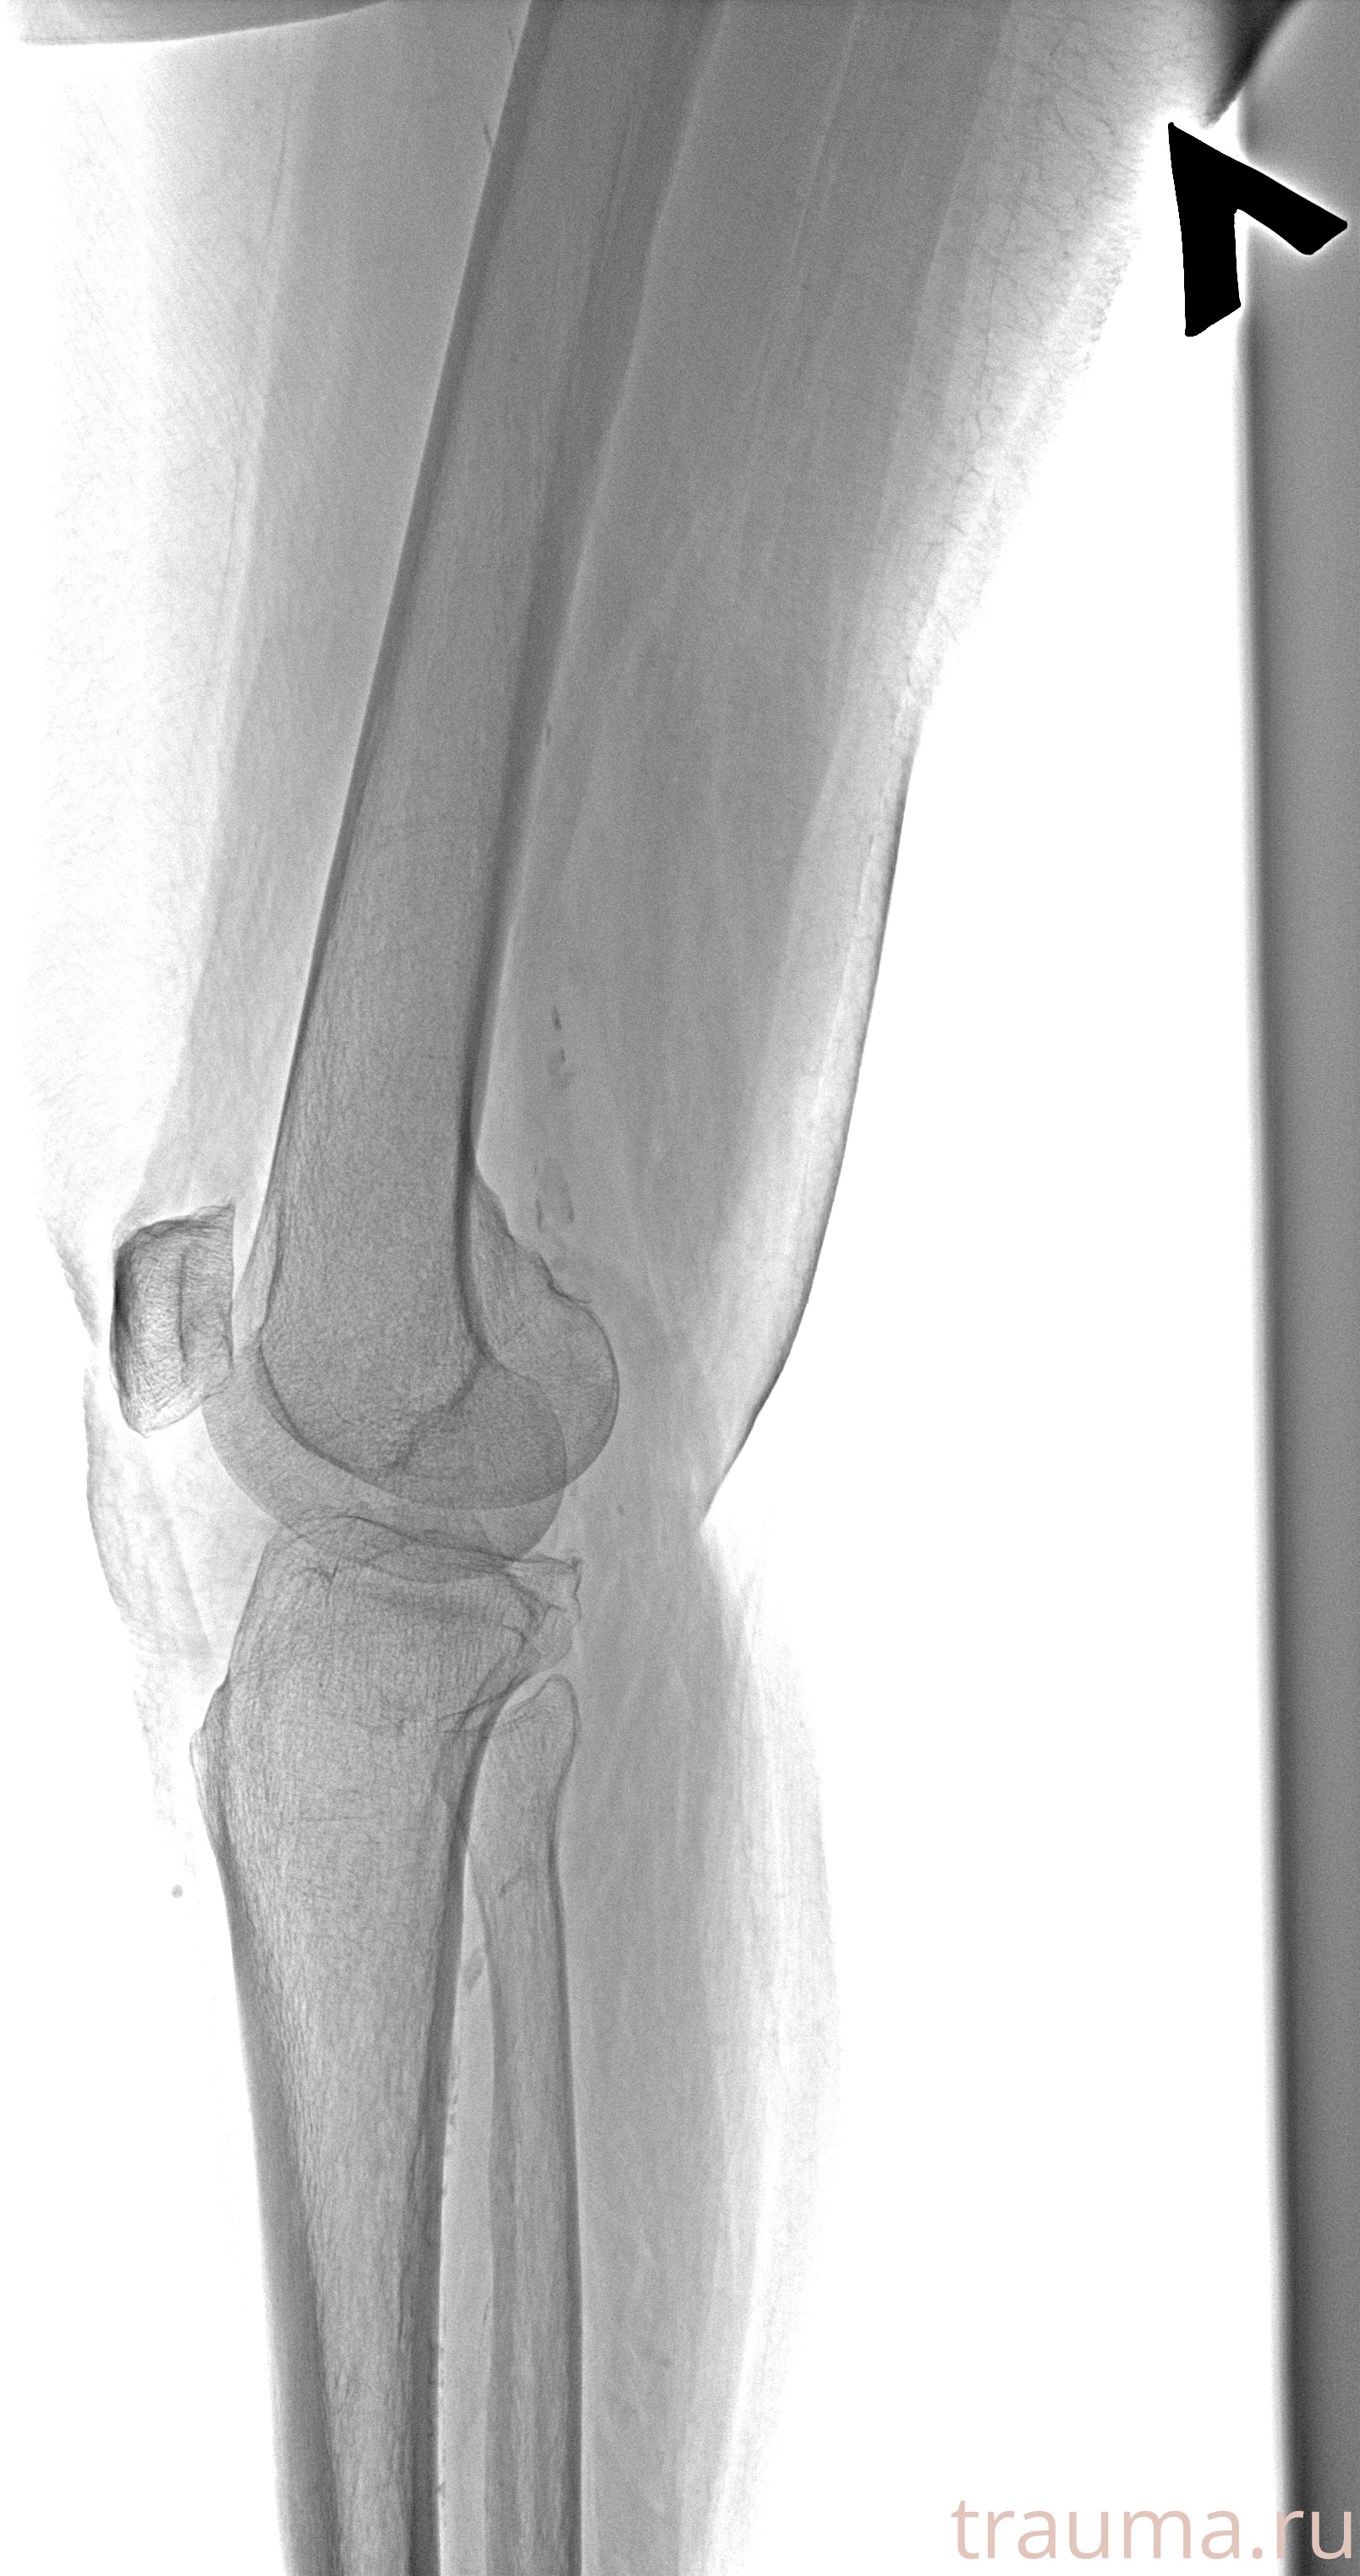

Рентгенограммы

Рентген на дому: по вашему адресу приезжает врач-рентгенолог, травматолог-ортопед с мобильным рентгеновским аппаратом, проводит диагностику травмы или заболевания, делает необходимые рентгенограммы, дает рекомендации по дальнейшему лечению. Получить качественные снимки в домашних условиях возможно благодаря уникальной методике, разработанной МосРентген Центром для института  Склифосовского